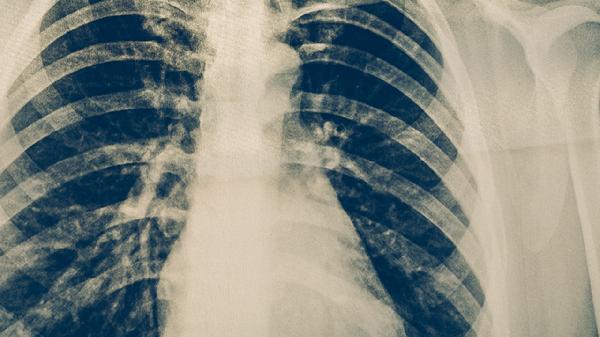

肺心病是怎么形成的

肺心病可能由慢性阻塞性肺疾病、肺动脉高压、低氧血症、肺部血管病变、先天性心脏病等原因引起,可通过氧疗、药物治疗、手术等方式干预。